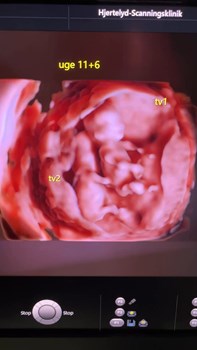

Se hele opslaget på Dyrehospitalet Heden ApS’ FacebooksideNakkefoldsscanning på enæggede tvillinger 👶💞👶 De kommende forældre gav sig selv en tidlig julegave og fik lavet nakkefold og risikovurdering på de 2 små uge 11+6. Fostrene er ca 50 mm i CRL længde...